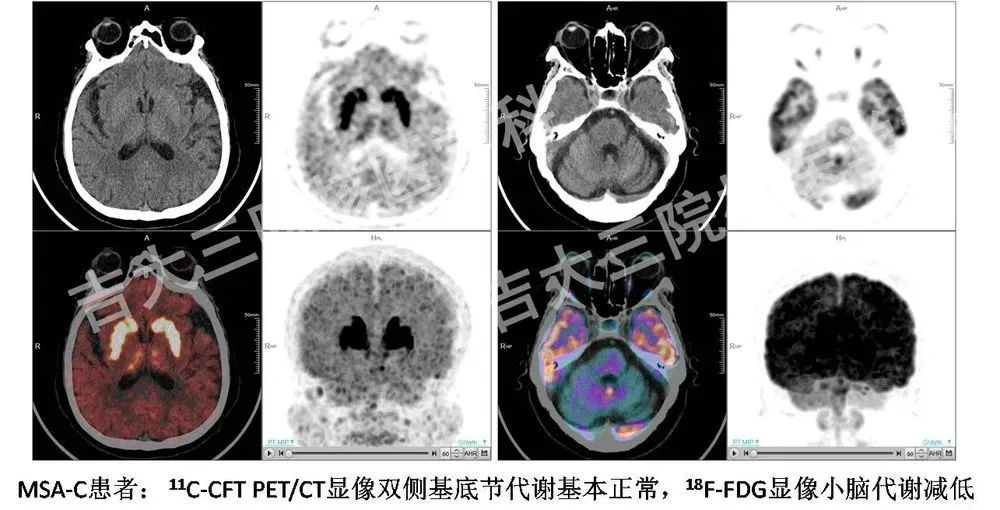

18F-FDG是目前最常用的、最成熟的顯像方法。腦以葡萄糖作為最主要能源,因此葡萄糖代謝可反映腦內(nèi)神經(jīng)元的活性。研究表明,PD與非典型PD綜合征患者不同腦區(qū)的葡萄糖代謝存在差異,因此可利用葡萄糖代謝成像進行鑒別診斷。典型PD腦內(nèi)基底節(jié)葡萄糖代謝相對保留,而雙側(cè)額葉前運動及輔助運動區(qū)呈低代謝。同時,在新的圖像處理技術(shù)、智能的自動化診斷程序幫助下,18F-FDG PET/CT顯像能夠在PD早期診斷中發(fā)揮更大的作用。

聯(lián)合DAT及FDG功能影像學(xué)手段有利于PD的早期診斷、鑒別診斷,彌補單一檢查的不足,從多個角度評估病理生理變化,對病情進行全面評價。目前,11C-CFT PET/CT顯像已在我國北京301醫(yī)院、上海華山醫(yī)院等多家三級甲等醫(yī)院展開應(yīng)用,在早期診斷PD方面取得了令人鼓舞的臨床效果。